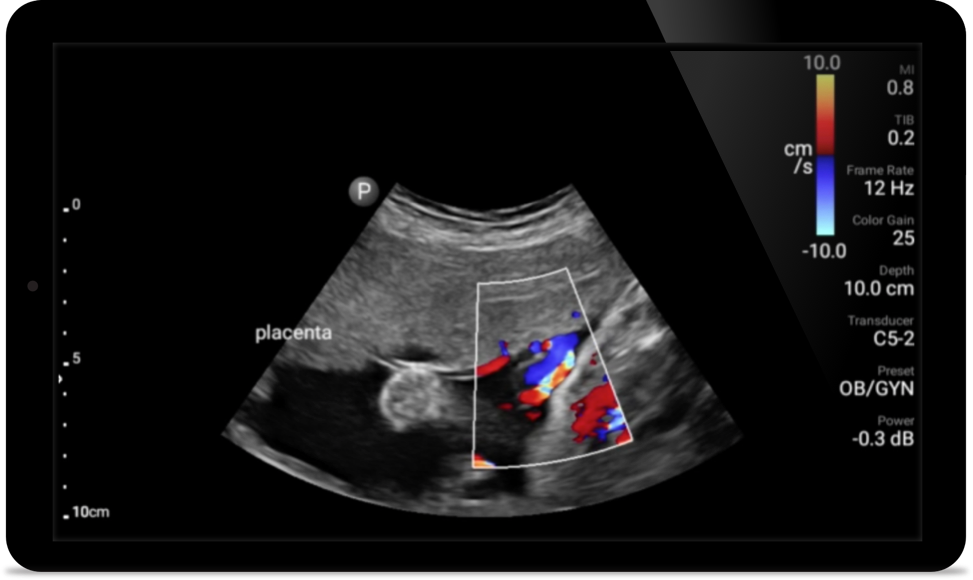

Las soluciones Lumify POCUS pueden ayudarle a detectar el tubo endotraqueal dentro de la tráquea, ayudar en los procedimientos de cricotirotomía emergentes, en el diagnóstico de derrame pleural y enfermedades alveolares intersticiales.

El uso de Lumify junto a la cama de sus pacientes puede ser una herramienta valiosa para determinar el estado del contenido estomacal y puede reducir el riesgo de aspiración pulmonar. En conjunto, esto puede reducir el riesgo de complicaciones por anestesia.

• Rango extendido de frecuencias de operación de 4 a 1 MHz • 2D, Doppler a color, Modalidad M, XRES avanzado e imágenes armónicas multivariables • Imagenología de alta resolución para aplicaciones abdominales y cardíacas: optimizaciones de preajustes de imágenes cardíacas, gineco-obstétricas, pulmonares, abdominales y FAST.